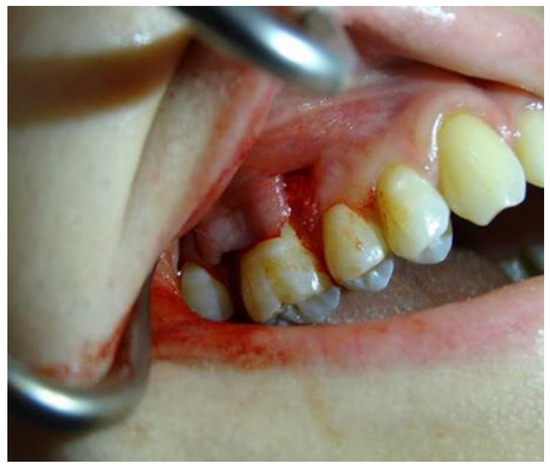

2.1.4. Surgical Procedures

3. Results